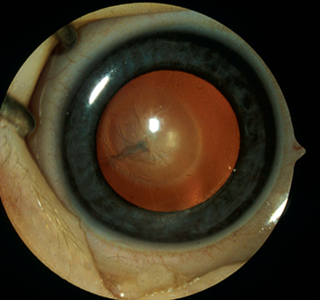

Persistent Fetal Vasculature

Persistent fetal vasculature (PFV) terjadi akibat adanya kegagalan regresi pada kompleks vaskular hialoid janin dan merupakan penyebab umum katarak pada bayi. Menilik ke masa lalu, Persistent fetal vasculature (PFV) biasa disebut dengan istilah Persistent hyperplastic primary vitreous (PHPV), namun dalam beberapa tahun terakhir, istilah Persistent Jetal vasculature karena dianggap lebih akurat, dan secara anatomi lebih mudah dikenali. Secara klinis, terdapat membran retrolental dengan berbagai ukuran yang kepadatannya yang menempel pada permukaan lensa posterior. Membran retrolental tersebut dapat berukuran kecil dan terletak di tengah atau dapat memanjang hingga menempel pada prosesus siliaris sejauh 360 dejarat. Seperti halnya pada katarak nuclear, Persistent fetal vasculature (PFV) bersifat bawaan. Ketika diamati, mata pada penderita Persistent fetal vasculature (PFV) hampir selalu bersifat mikroftalmik (mikrokornea) sampai pada tingkat tertentu. Persistent fetal vasculature (PFV) hampir selalu unilateral. Pembuluh hialoid yang persisten dapat menghubungkan membran retrolental ke saraf optik, namun sering kali pembuluh hialoid mengalami regresi sehingga hanya menyisakan membran. Dalam kasus yang parah, lensa bisa terdorong ke depan, menekan bilik mata depan, dan menyebabkan glaukoma sekunder. Glaukoma dapat terjadi secara akut karena munculnya kekeruhan total yang masif serta pembengkakan lensa yang terjadi dalam beberapa hari, atau dapat berkembang secara bertahap selama bertahun-tahun. Persistent fetal vasculature (PFV) dapat pula  berhubungan dengan kelainan retina yang dapat berdampak buruk pada prognosis visual.